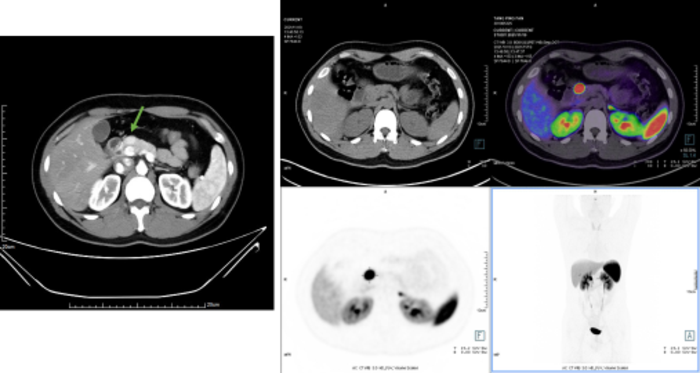

胰腺神经内分泌肿瘤(pNET),大部分为实性,但也有发生囊性变,形态学表现多样,需要与其它类型的胰腺肿瘤进行鉴别,在没有病理,没有68Ga和18FDG PET双扫描的情况下,如果贸然放弃或手术都不适合。影像学上,富血供是最具特征的,表现为增强后整体或周边明显强化、或囊实性病灶伴强化结节。病理主要靠免疫组化,AE1/3,CgA,CD56,SYN,E-cad阳性,β-catenin膜阳性。当G3级NET与NEC难以鉴别时,可进行基因突变检测,一般而言,NEC 往往具有 P53 基因突变和(或)RB 基因缺失,胰腺 NET 可能存在 MEN1、ATRX、DAXX基因突变。(下图为一例典型的pNET G2,左上为增强CT表现,右上为68Ga-DOTATATE PETCT表现,下方为病理免疫组化结果)